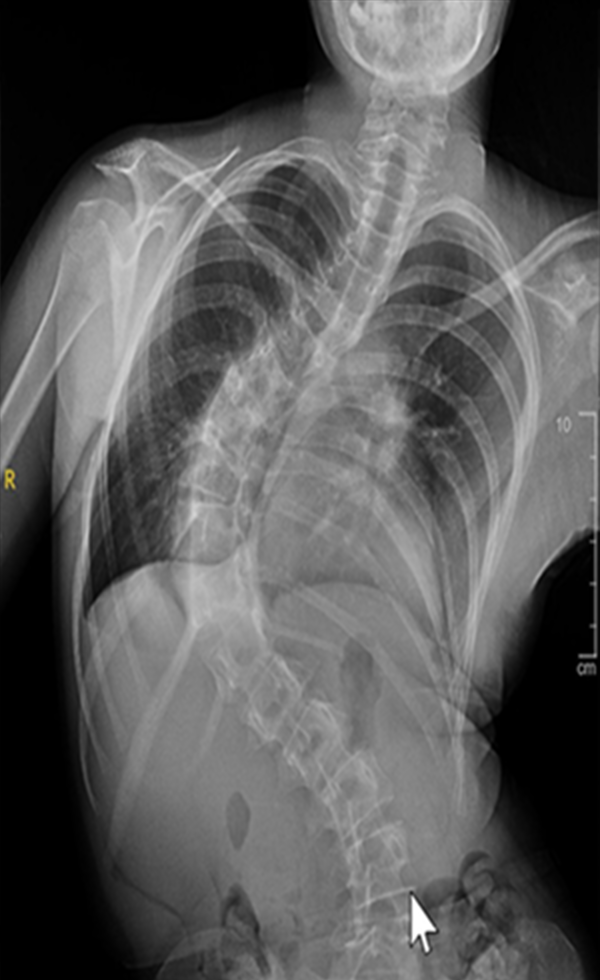

Scoliosis is a common condition characterized by a sideways curvature of the spine, often emerging during puberty. While its origins can vary, most cases are mild. However, without proper attention, severe deformities may lead to significant functional disabilities, impacting lung function and overall well-being.

Gallery : Before - After

After

Before